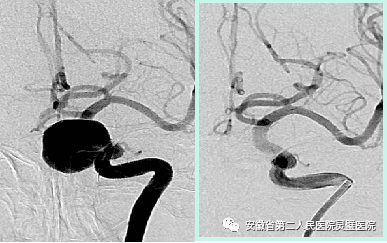

脑血管病亚专业组紧跟国际前沿,目前全面开展颅内动脉瘤、脑动静脉畸形、硬脑膜动静脉瘘等脑血管病的外科及血管内治疗,尤其对复杂颅内动脉瘤,灵活运用支架及球囊辅助、双微导管、液态栓塞剂栓塞、覆膜支架等技术,取得良好效果。开展烟雾病血管搭桥、颈内内膜剥脱术等脑血管外科手术。

前交通动脉瘤术前和术后

颈内动脉动脉瘤术前和术后

动静脉瘘术前和术后